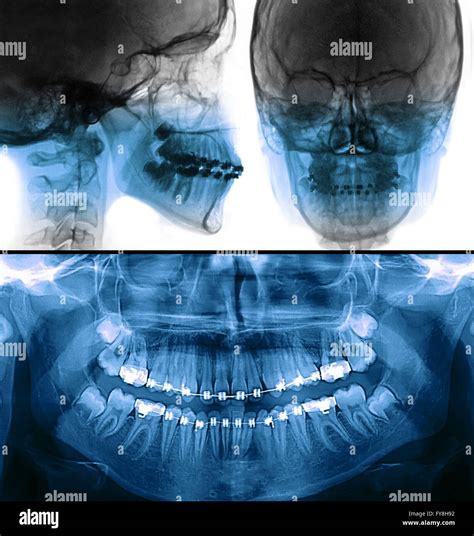

When you visit your dentist for a comprehensive oral health assessment, they may recommend a specialized imaging procedure to get a complete picture of your dental structures. This is where a dental panoramic X-ray, often referred to as an orthopantomogram (OPG), becomes an invaluable tool. Unlike traditional bitewing X-rays that focus on a few teeth at a time, this diagnostic technique captures a wide, sweeping view of your entire mouth, including the teeth, upper and lower jaws, jaw joints (TMJ), and surrounding structures, all on a single film or digital image.

A dental panoramic X-ray is a two-dimensional imaging technique that rotates around the patient’s head to produce a comprehensive image of the oral cavity. Because it captures so much information in one scan, it provides dentists with a broader diagnostic perspective than localized images. It is commonly used in various areas of dentistry, ranging from general checkups to specialized treatments like orthodontics and oral surgery.

The technology behind this scan is fascinating. The X-ray source and the digital sensor move in a synchronized manner around the patient, who remains stationary during the process. This creates a panoramic projection that flattens the curved structure of the dental arches onto a single flat plane, allowing the dentist to examine the complex anatomical landscape of the mouth with ease.

While a dental panoramic X-ray is an excellent diagnostic tool, it is not always a substitute for more detailed imaging techniques. Because it is a two-dimensional image of a three-dimensional structure, there can be some distortion or magnification issues.